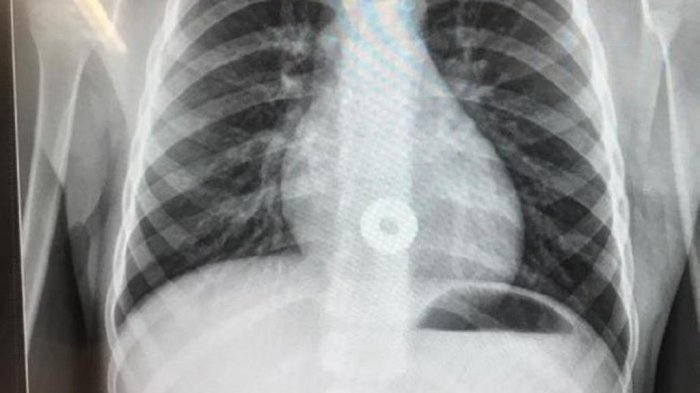

Karena merasa ketakutan dan kesakitan, bocah tersebut kemudian dibawa ke RS Royal North Shore, di mana ia dipindai menggunakan sinar X.

Koin pipih itu didapati berada dalam perutnya.